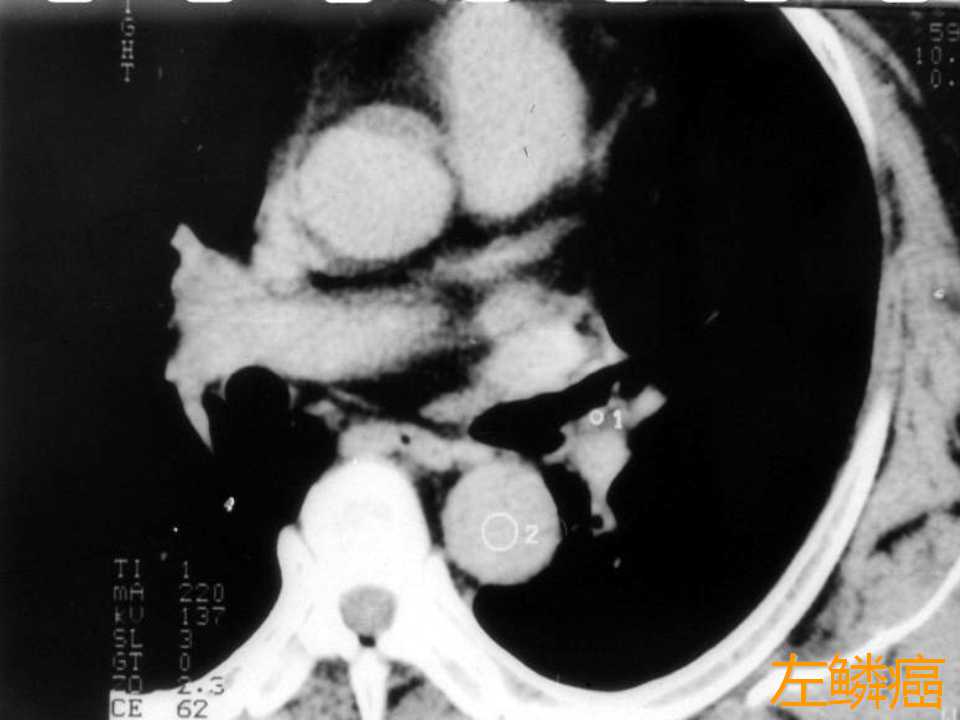

肺癌影像学表现